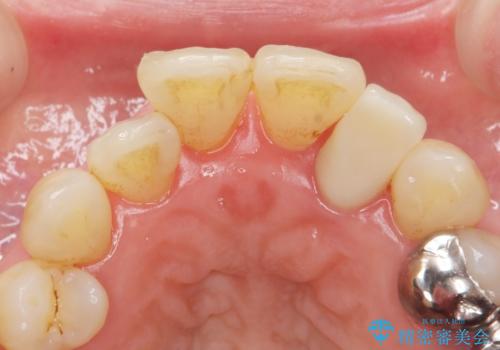

- 下の前歯(左下2)と奥歯の動揺がひどくなってきたことを主訴に来院された患者様です。

精査したところ、前歯の咬み合わせが反対になっていること、下の奥歯(下顎両側67)が4本欠損していることから動揺が生じていました。

入れ歯も抵抗があるとのことから、相談を重ね、今の状態では保存不可能な下の前歯(左下2)を抜去し、ブリッジや連結補綴により動揺を抑えることにしました。

また、咬み合わせが反対になっている上の前歯(左上2)も補綴で形を変えることにより、咬合を改善しました。